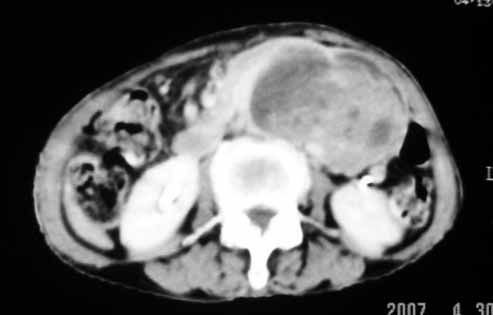

以下是引用天南地北在2007-4-30 17:42:00的发言:[br]增强扫描显示腹主动脉给包绕、推移。肿块不规则强化,[br]修正我在平扫的诊断[br]支持考虑:间叶源性肿瘤可能性大

以下是引用余辉在2007-4-30 18:01:00的发言:[br]病灶前方的条状增强影是什么?若是胰腺,位置似乎有点低,若是十二指肠,似乎又不诫该是那样强化,姑且将其看作胰腺吧,那么考虑来源于胰腺粘液囊腺瘤可能性大,其次考虑来源于肠系膜或者后腹膜的肿瘤如平滑肌肉瘤,异位嗜铬细胞瘤及淋巴瘤等。

以下是引用zyx168在2007-4-30 23:24:00的发言:[br]考虑:间叶源性肿瘤可能性大